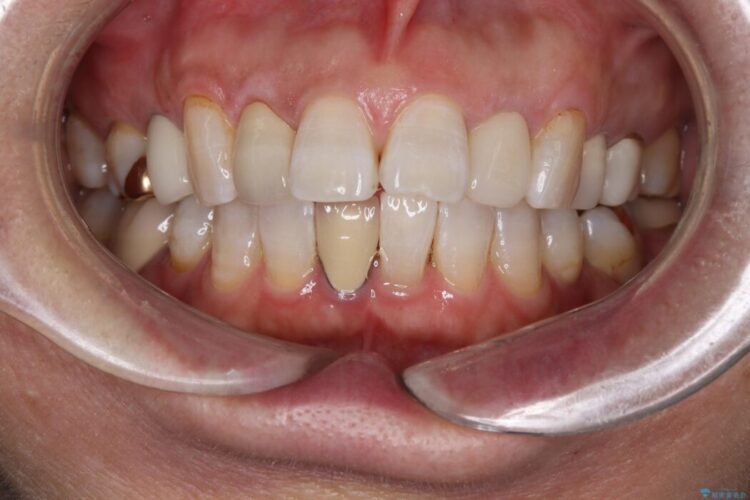

破折したセラミックインレーのやり替え

他院で装着されたセラミックインレー(MOD窩洞)が破折したとご来院されました。

治療期間(治療回数):1ヶ月(2~5回) | 概算治療費:15.4万円(税込)(オールセラミッククラウン14.3万円+仮歯1.1万円)